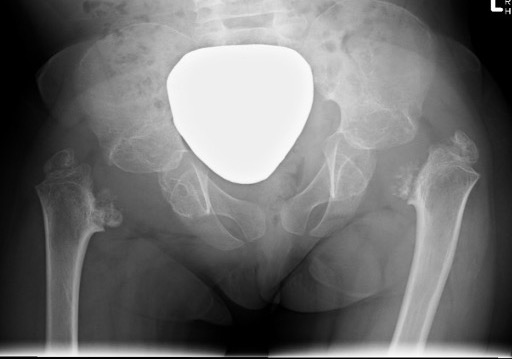

Xray

| Varus femoral neck | Inverted Y | Hilgenreiner's epiphyseal angle |

Neck-shaft angle < 125°

Normal is 150° in infant |

Inferior sclerotic metaphyseal triangle

Pathognomonic of developmental |

Angle between Hilgenreiner's & physeal line

Normal < 25°

|